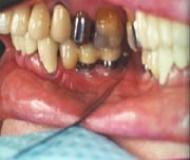

El primer paso es la instalación de los implantes

dentarios en el maxilar.

El segundo

paso, luego de una espera de 3 a 4 meses,

se colocan unos intermediarios a través de la encía, que son los que sostendrán

la futura prótesis.

El tercer y último paso es la colocación del sistema

protésico elegido, sobre los intermediarios colocados en el segundo paso, en

forma firme y precisa.